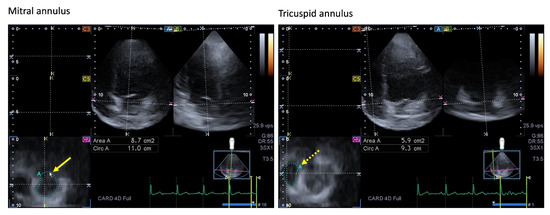

- Nemes, A.; Rácz, G.; Kormányos, Á. Tricuspid Annular Abnormalities in Isolated Left Ventricular Non-compaction-Insights From the Three-dimensional Speckle-Tracking Echocardiographic MAGYAR-Path Study. Front. Cardiovasc. Med. 2022, 9, 694616. [Google Scholar] [CrossRef]

| Mitral valve | MA was dilated and functionally impaired. | [87] | 20 |

| Tricuspid valve | TA was dilated, with preserved sphincter-like function. | [18] * | 21 |